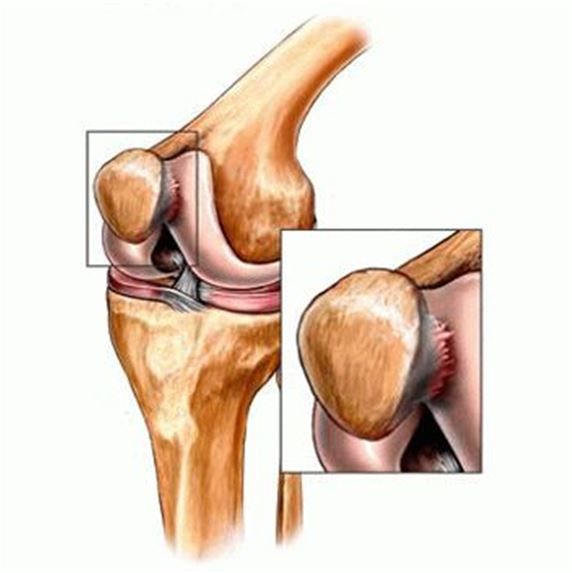

Хондропатия надколенника

Заболевание также чаще всего диагностируется у мальчиков 10-14 лет. Хондропатия надколенника развивается в области крепления сухожилий к коленной чашечке, препятствуя поступлению питательных веществ из синовиальной жидкости к хрящевым тканям. Ведущие симптомы патологии — спонтанные боли, выраженность которых повышается при движении или при пальпации коленной чашечки. Если в полости сустава накапливается выпот, то кожа над ним разглаживается, краснеет, становится горячей на ощупь. Длительность течения этого вида хондропатии — несколько месяцев. Интенсивность болевого синдрома постепенно снижается, а затем происходит полное восстановление поврежденных структур.